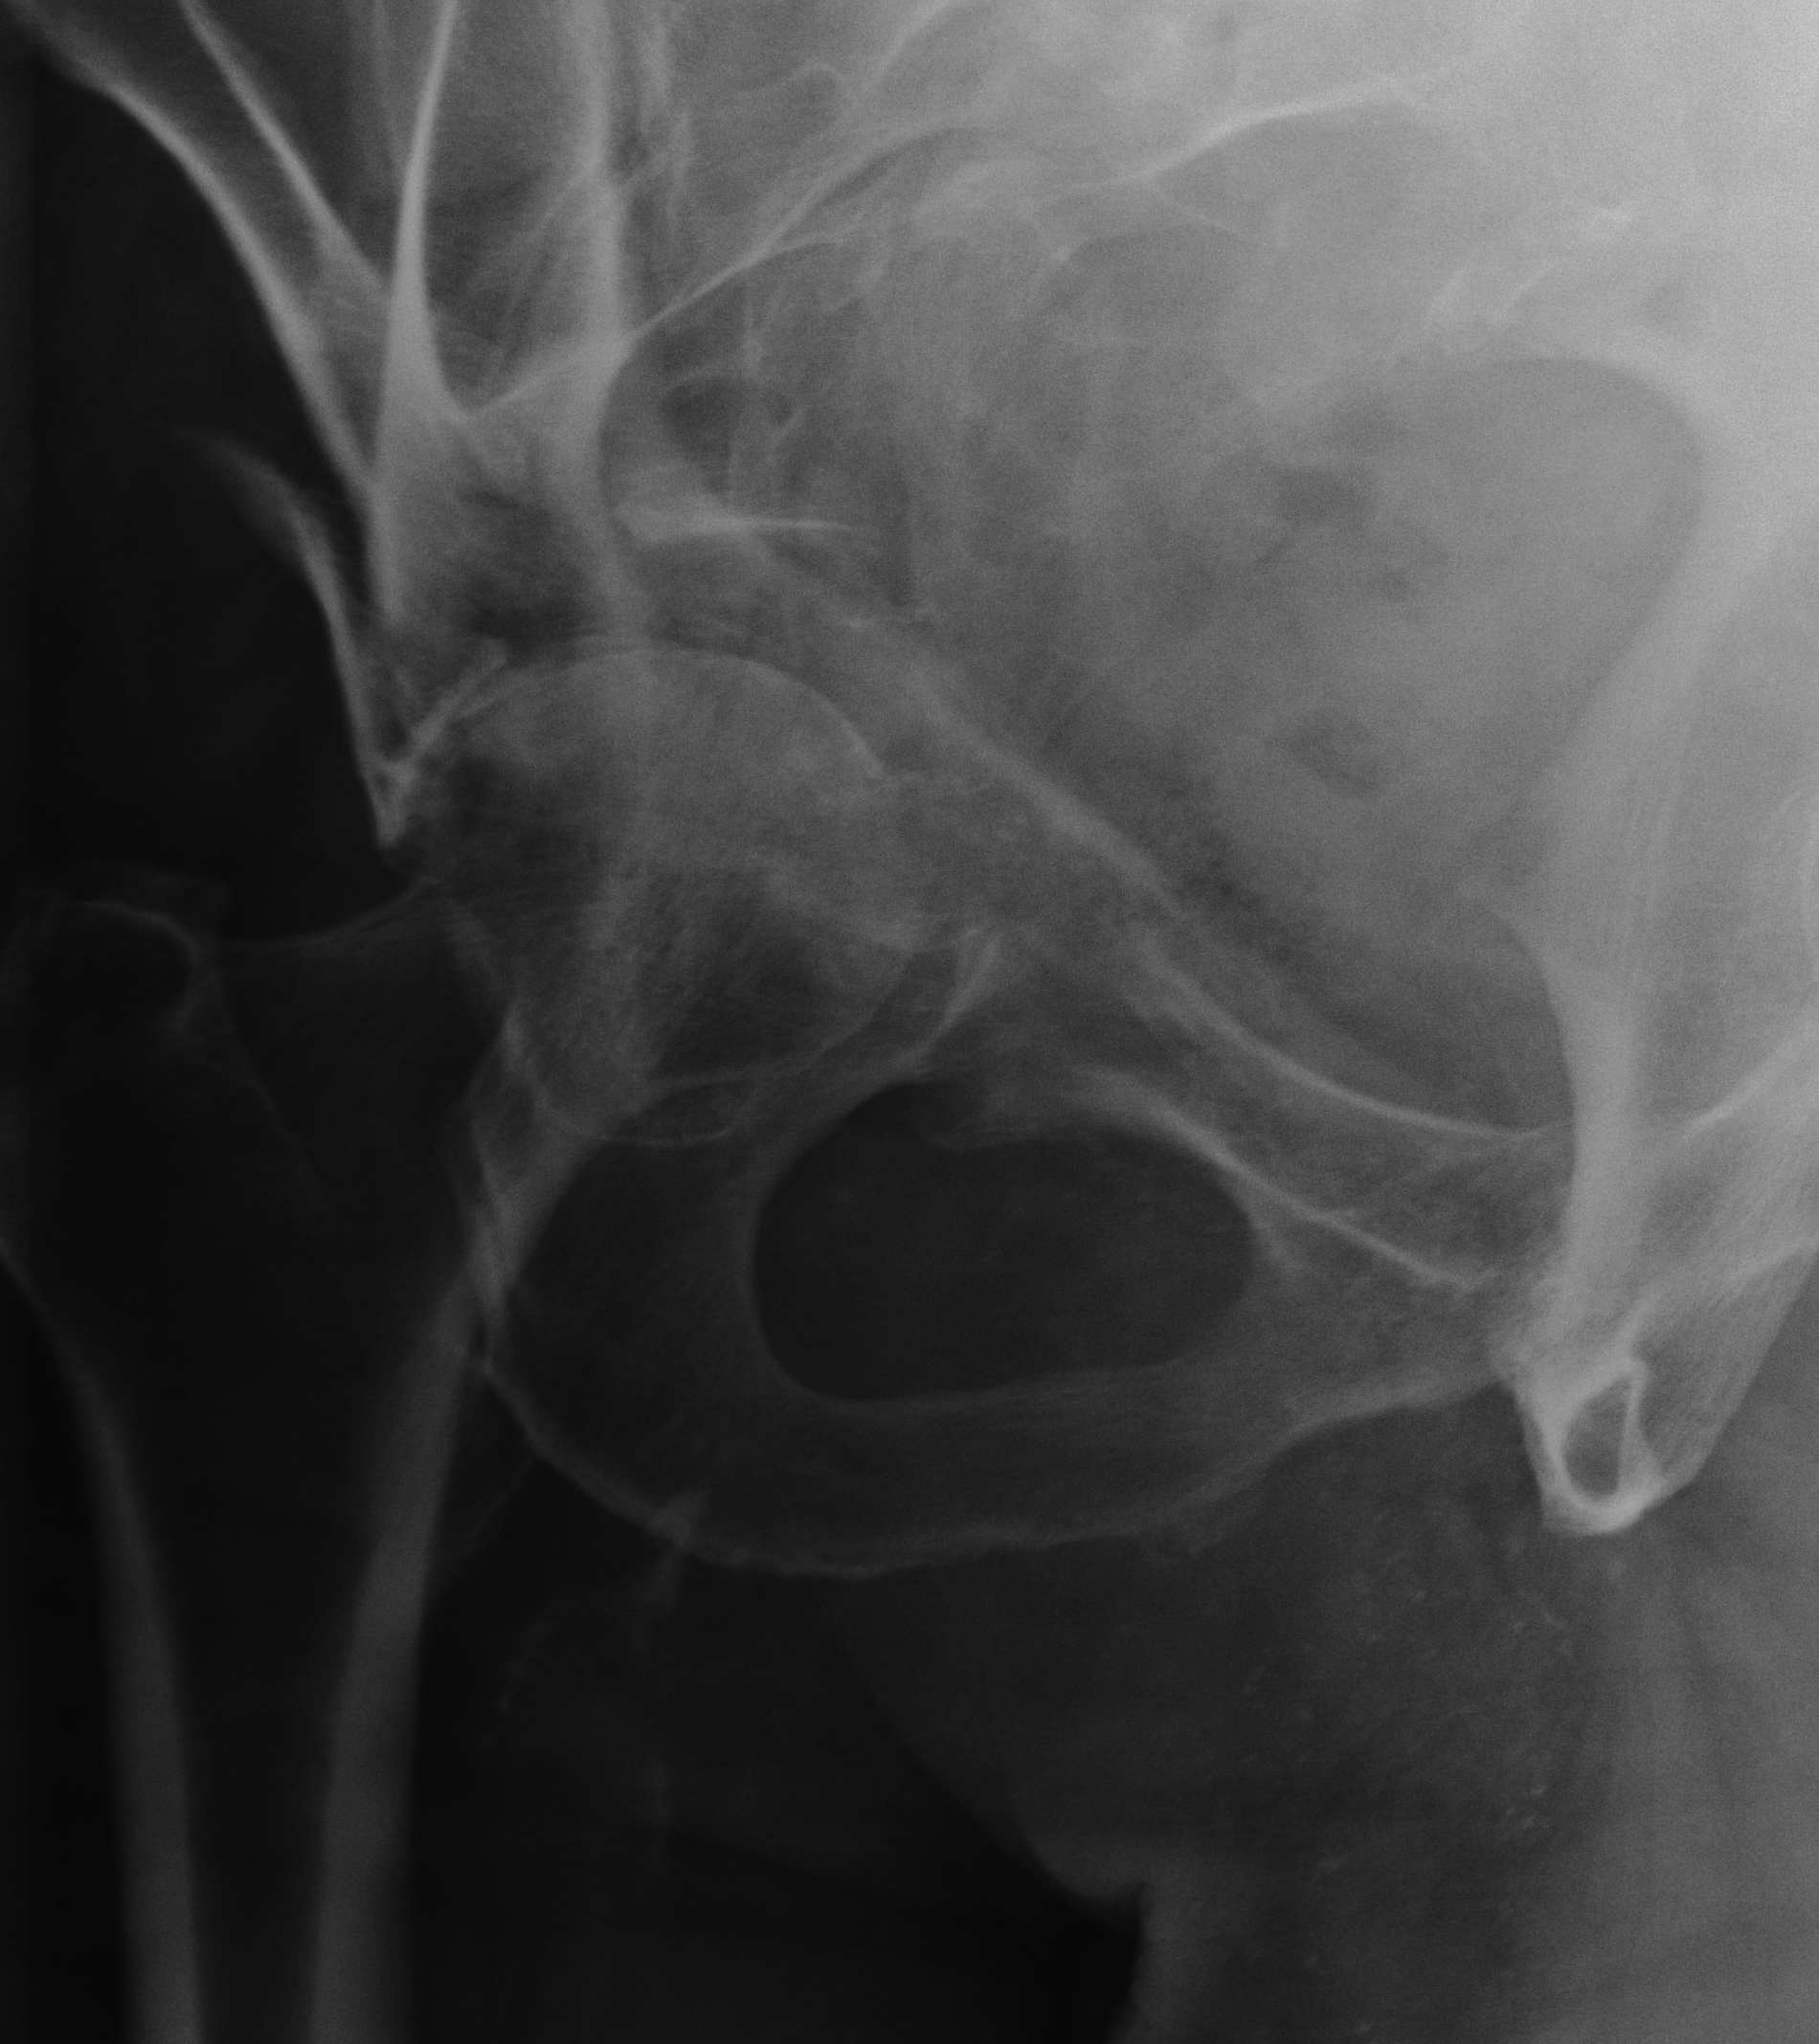

Judet views / 45o obliques

Internal Oblique / Obturator Oblique

- affected side rotated forward

- anterior column + posterior wall

External Oblique / Iliac Oblique

- unaffected side rotated forward

- posterior column + anterior wall